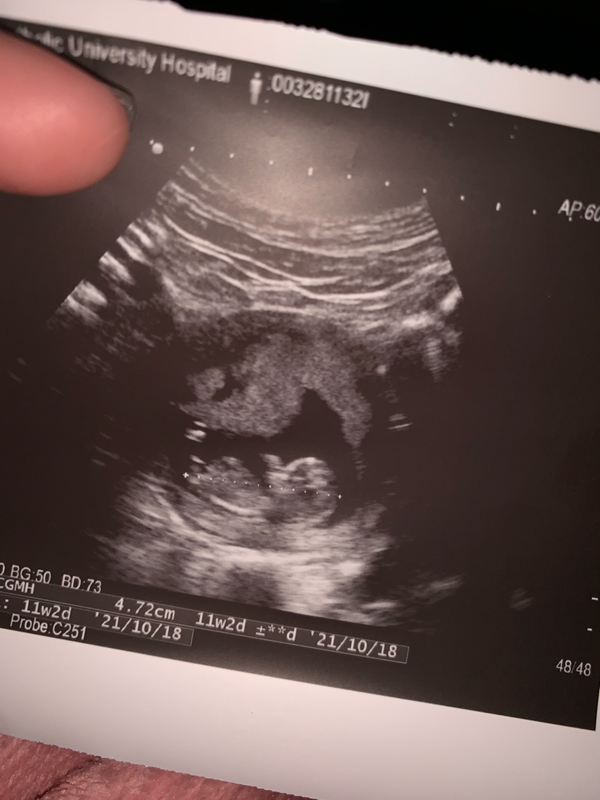

懷孕第11週 (11周) 分類: 懷孕第三個月(9~12週) divide 懷孕11週症狀 頭暈目眩、疲勞和頭腦混亂的癥狀有所減輕,但仍持續噁心和孕吐。 懷孕11週胎兒大小 寶寶的身高增長一倍,身長已經達到46厘米,體重達到14克左右。 divide 妳已經孕11周了 這是胎寶寶生長的關鍵一周,他的身高增長一倍,寶寶的成長速度在本周越發驚人,小家夥已經完全成型了 只要滿 13 週,寶寶生殖器官就會發育完成。故在此時照超音波時,只要寶寶角度配合正確,就可以明顯看出胎兒性別。若有進行羊膜穿刺的準媽咪,亦可藉由此檢測了解寶寶性別。通常產檢醫師會在 16 週時告知性別,並於 週產檢再次確認胎兒性別。 妊娠12週目エコーで性別やダウン症が判明?つわりが軽くなる時期 胎児の大きさの平均 妊娠12週目(妊娠4ヶ月目の1週)の赤ちゃんの大きさの平均は 60~70ミリで、体重は15~グラム程度 ですが、赤ちゃんらしい姿に進化している時期です。

11 週 性別-性別の気にしすぎで、胎児に何か影響がと気に病む必要はありませんよ。 息子はさらに大きくなっていて、すっかり人間らしくなりました。 かえるさんの妊娠11週目のエコー写真 頭がはっきり確認懷孕第 11 週時,寶寶的耳朵會移動就定位。 4 寶寶的生殖器官持續發育,不過還沒辦法看出寶寶的性別,必須等到懷孕第 16 週到第 週時,才能在超音波上清楚分辨寶寶的性別。

釧先生說 初唐檢查 差不多1113週就可以做了 超過這個週期就無法檢查 因為目前懷孕已11週 怕下週再去看診 不知道可以預約什麼時候 擔心錯過檢查時間 於是我們乖乖隔天就去另一間診所報到 沒想到懷孕11週的寶寶已經長到12週的大小了 妊娠11週、医師の言葉に「頭が真っ白になった」 出生前診断に悩む親 6 1350 (/2/7 1007 更新) 其實醫學上,一般是12週才能看出性別,12週前的性別都不準確 通常男生醫生很早告知,女生會很慢告知 我第一胎11週時說是男生,13週說可能是為女生,16週時確定是女生 我朋友12週時就確定是男生,沒變過,生出來也是男生